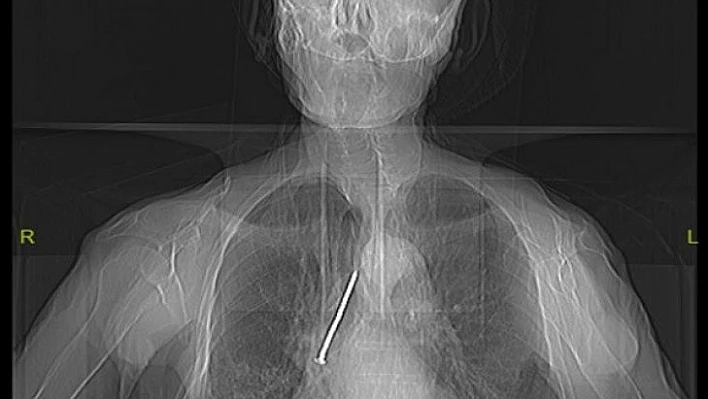

Elazığ’da, boynundan nefes borusuna açılan açıklık aracılığıyla solunumunu sağlayan Keko Ateş (91), öksürük ve nefes darlığı şikayetiyle Fethi Sekin Şehir Hastanesine başvurdu. Burada yapılan tetkik ve muayeneler sonucu yaşlı adamın nefes alıp verdiği boşluğu temizlemek için kullandığı 10 santimetrelik çivinin soluk borusuna kaçtığı belirlendi. Hayati tehlike oluşturan çivi, Göğüs Cerrahi Uzmanı Dr. Öğretim Üyesi Murat Kılıç tarafından “Rijit Bronskoskopi” işlemi ile çıkarıldı. Yaşlı adam çivinin çıkarılmasından kısa süre sonra hasta taburcu edildi.

Hızlı bir şekilde müdahale edilmediği takdirde hayatı tehlikeye atabilen bir durumla karşı karşıya kaldıklarını belirten Dr. Kılıç, "Larenks kanseri nedeniyle 24 yıl önce boynundan nefes borusuna açılan açıklık aracılığıyla nefes alıp verebilen hasta, nefes borusundaki bu açıklığı temizlemek amacıyla kullandığı 10 santimlik çiviyi soluk borusuna kaçırmış. Bu nedenle gelişen öksürük ve nefes darlığı şikayeti ile önce başka bir sağlık merkezine başvurmuş, ardından Fethi Sekin Şehir Hastanemiz Göğüs Cerrahisi Kliniğine yönlendirilmiş. Biz de hastanede 91 yaşındaki hastamıza çektiğimiz tomografide soluk borusu içerisinde, sağ akciğer içerisine doğru kaçmış olan çiviyi tespit ettik” dedi.